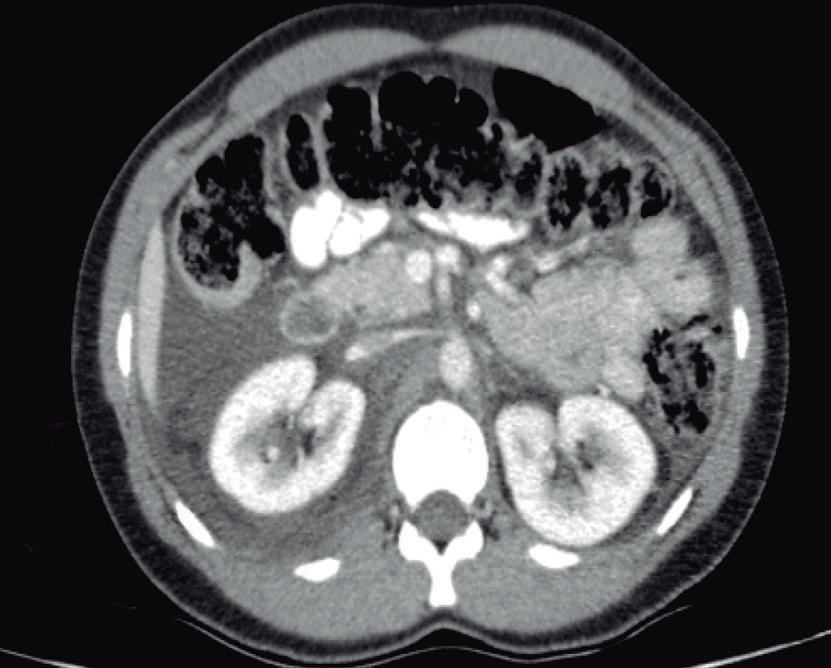

La endoscopía superior es un procedimiento fundamental para el diagnóstico, la evaluación de la respuesta al tratamiento y el monitoreo a largo plazo de la actividad de la EEo. Los hallazgos endoscópicos típicos incluyen edema (reducción de vascularidad), anillos esofágicos fijos, exudados blancos, surcos longitudinales, estenosis, estrechamiento de la luz esofágica, friabilidad de la mucosa (mucosa en papel crepé) y una consistencia firme de la mucosa al realizar biopsias (signo de “tracción" o "resistencia”) en pacientes con fibrosis (Figura 1). Estos hallazgos no son patognomónicos y no constituyen un criterio diagnóstico; sin embargo, cuando se evalúa de forma cuidadosa, en la gran mayoría de los casos se pueden observar.19-21

En el panel A se observa un esófago con edema difuso y pliegues longitudinales; en el panel B se aprecia edema con pliegues y exudados blanquecinos; en el panel C se evidencia un estrechamiento luminal acompañado de anillos esofágicos y exudados; y en el panel D se muestra un desgarro mucoso posterior a la dilatación con bujía de Savary, hallazgo esperado tras este procedimiento terapéutico.

Figura 1. Características endoscópicas de la esofagitis eosinofílica